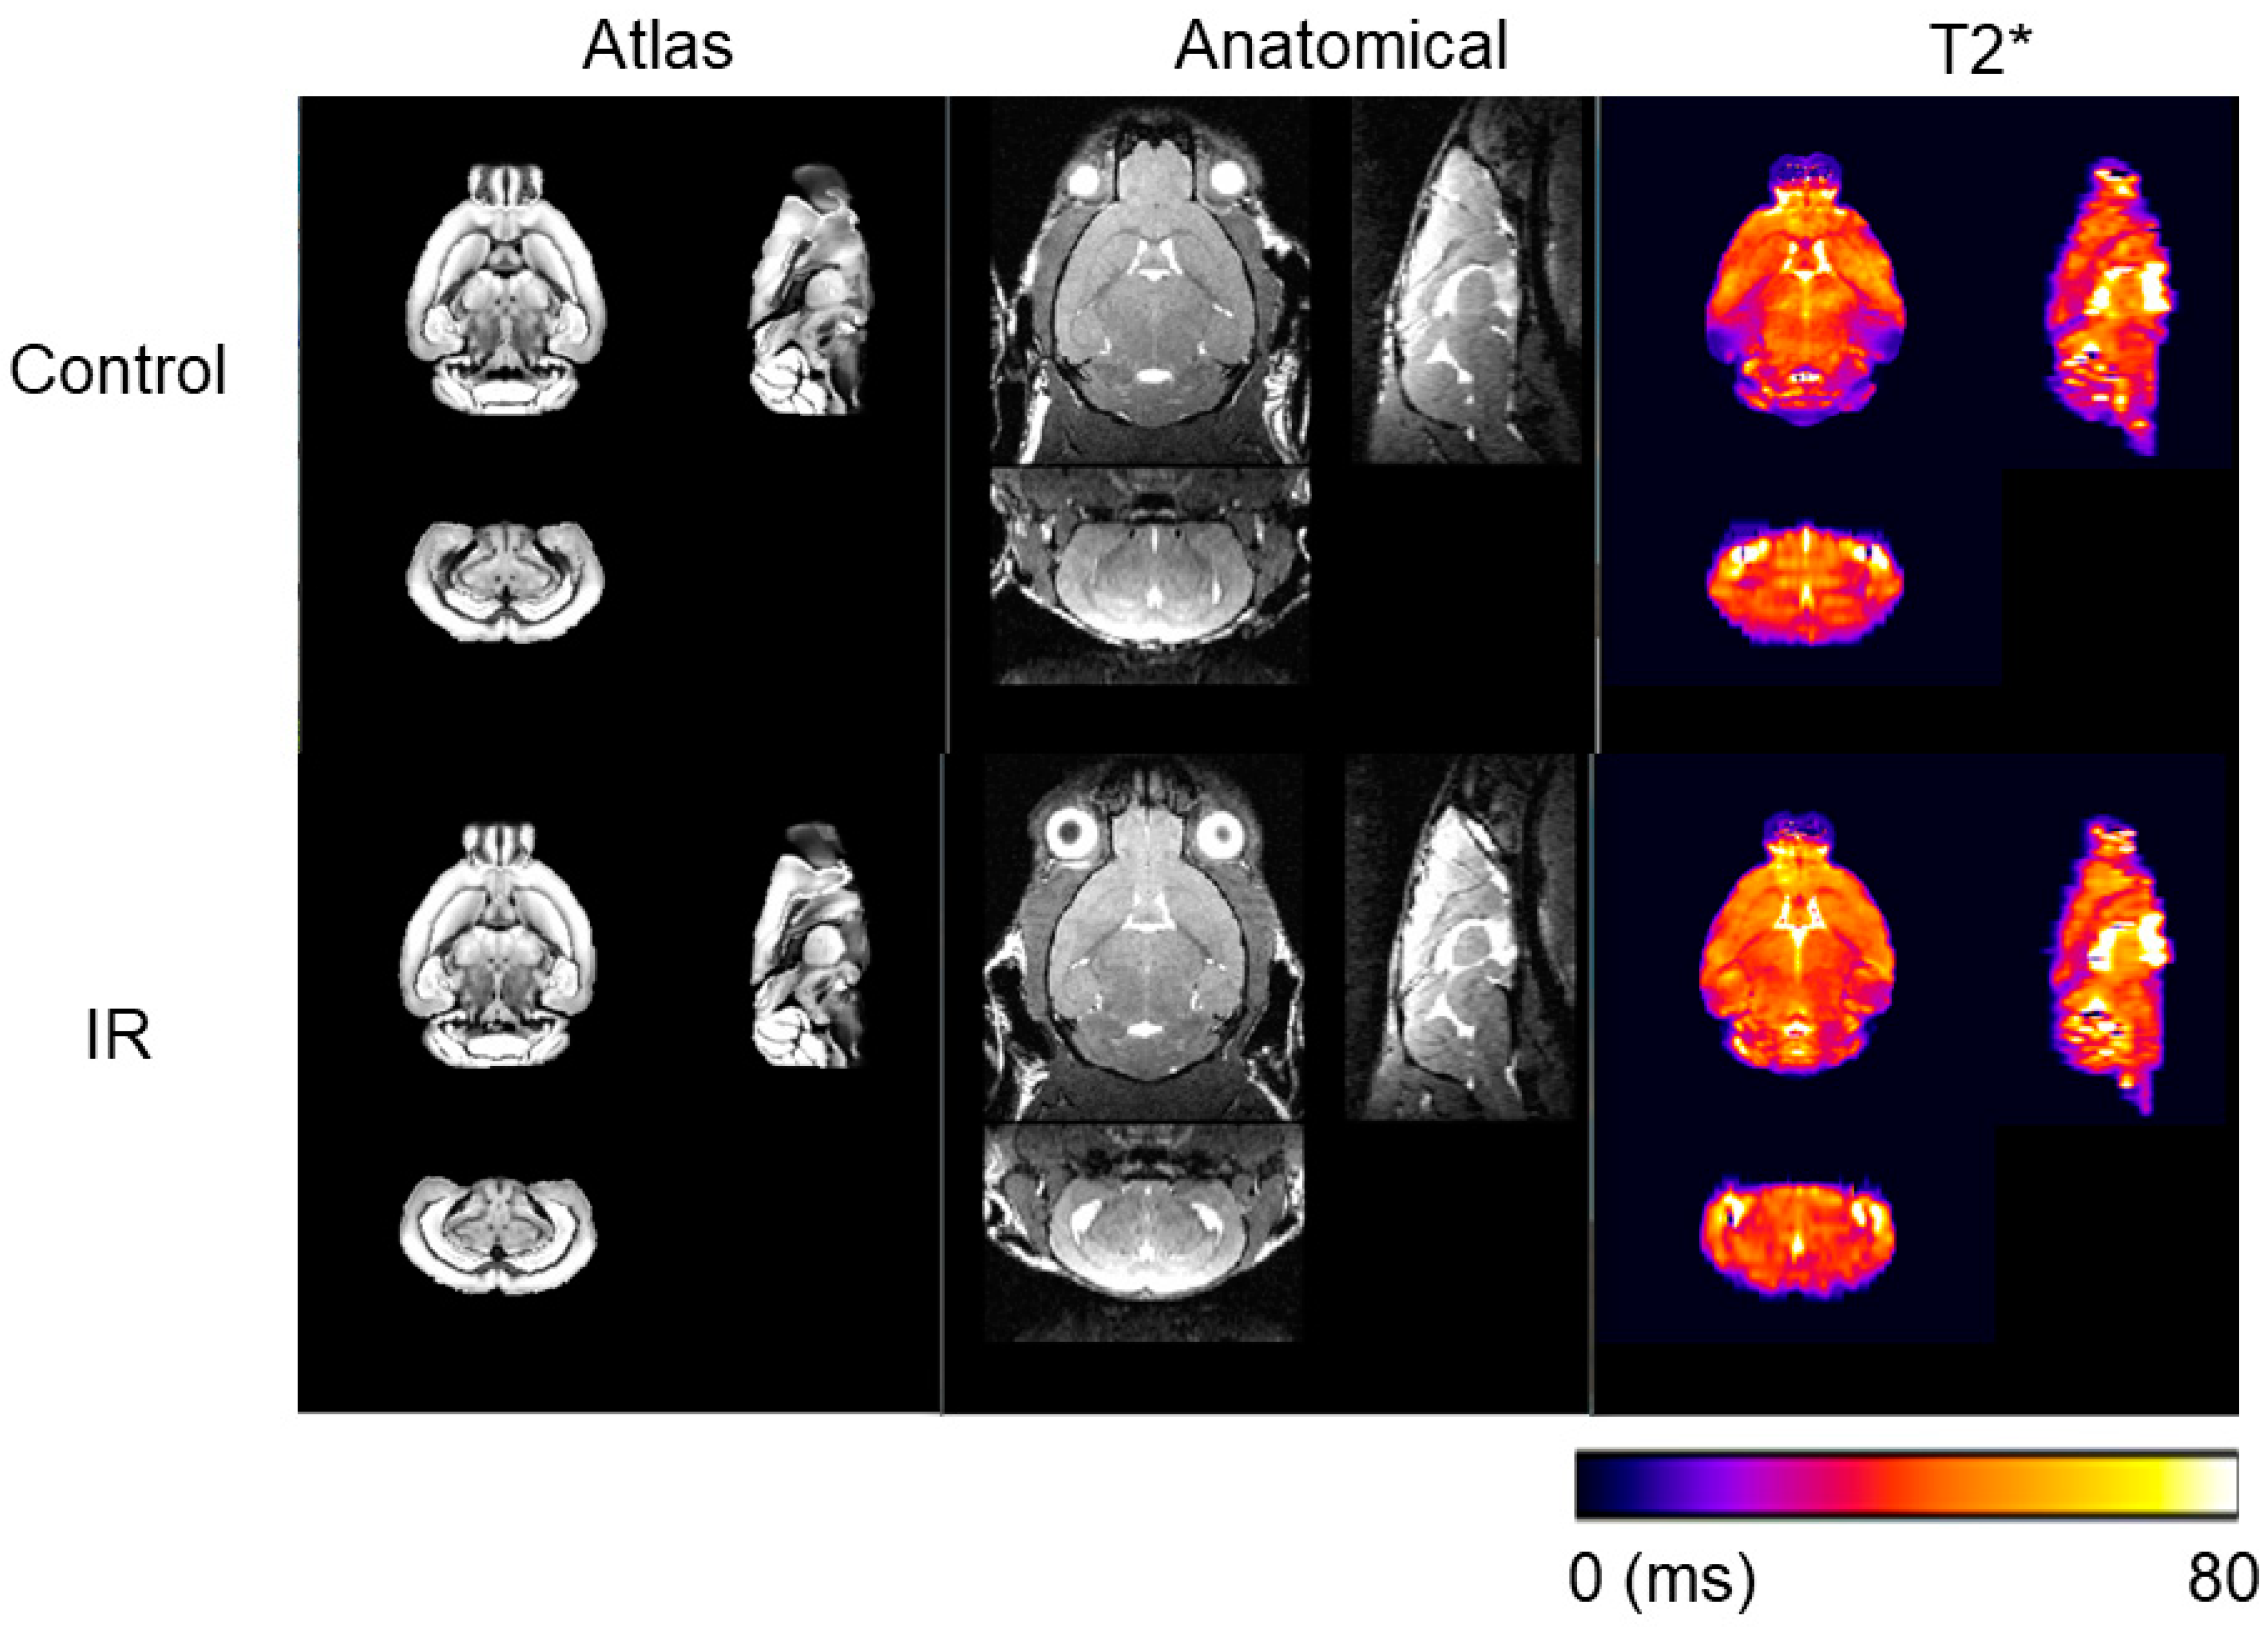

2.2. Magnetic Resonance Imaging (MRI) Data Acquisition and Processing

3. Results